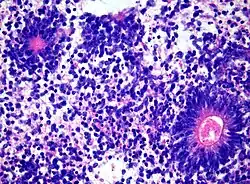

Histology of Medulloepithelioma

The World Health Organization has classified the central nervous system primitive neuroectodermal tumors into five subtypes: neuroblastoma, ganglioneuroblastoma, medulloepithelioma, ependymoblastoma, and not otherwise specified PNET.[1] The last one encompasses the PNETs with varying characteristics that hasn't been well defined yet.[1] Neuroblastomas are PNETS that involve the process of cell differentiation into neurons,[1][2] while ganglioneuroblastomas are PNETs that involve ganglion cells.[1]

Medulloepithelioma, on the other hand, are tumors involving the constant cell division on the epithelium tissue where bundle of neuron endings are located.[1] Such tissue will differentiate into a similar form as the embryonic neural tube, also known as the starting structure of the central nervous system.[1][2][3] Medulloepitheliomas also present a pattern known as rosettes, characterized by the arrangement of a bundle of cells into circular shapes and around a center or a neuropil.[1] Ependymoblastoma also present rosettes as well as a higher density of cells.[1][3] It involves the process of differentiation into ependymal cells.[2][3]

Rosettes in Ependymoblastoma histology

Further classification types have come up but not yet approved by the World Health Organization.[1] The term "embryonal tumor with abundant neuropil and true rosettes", or ETANTR, has been proposed as a sixth subtype of PNET.[1] However, the still unofficial term "embryonal tumor with multilayered rosettes" (ETMR) has been more frequently used and encompasses ETANTRs, medulloepitheliomas, ependymoblastomas, and variants of PNETs with presence of rosettes and with no well defined classification.[3]